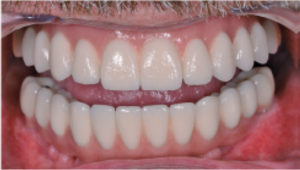

Resultado estético final tras la colocación de la prótesis definitiva, a un paciente con línea de sonrisa alta, sin compromiso visual de los accesos de tornillo. Caso clínico publicado originalmente en la revista científica Dentale Implantologie, Vol. 23, nº 2 (2019).